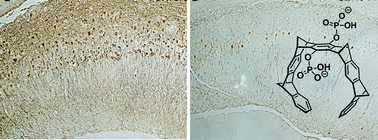

Molecular tweezers represent the first class of artificial receptor molecules that have made the way from a supramolecular host to a drug candidate with promising results in animal tests. Due to their unique structure, only lysine and arginine are well complexed with exquisite selectivity by a threading mechanism, which unites electrostatic, hydrophobic and dispersive attraction. However, tweezer design must avoid self-dimerization, self-inclusion and external guest binding. Moderate affinities of molecular tweezers towards sterically well accessible basic amino acids with fast on and off rates protect normal proteins from potential interference with their biological function. However, the early stages of abnormal Aβ, α-synuclein, and TTR assembly are redirected upon tweezer binding towards the generation of amorphous non-toxic materials that can be degraded by the intracellular and extracellular clearance mechanisms. Thus, specific host–guest chemistry between aggregation-prone proteins and lysine/arginine binders rescues cell viability and restores animal health in models of AD, PD, and TTR amyloidosis.

Graphical abstract: Molecular tweezers for lysine and arginine – powerful inhibitors of pathologic protein aggregation